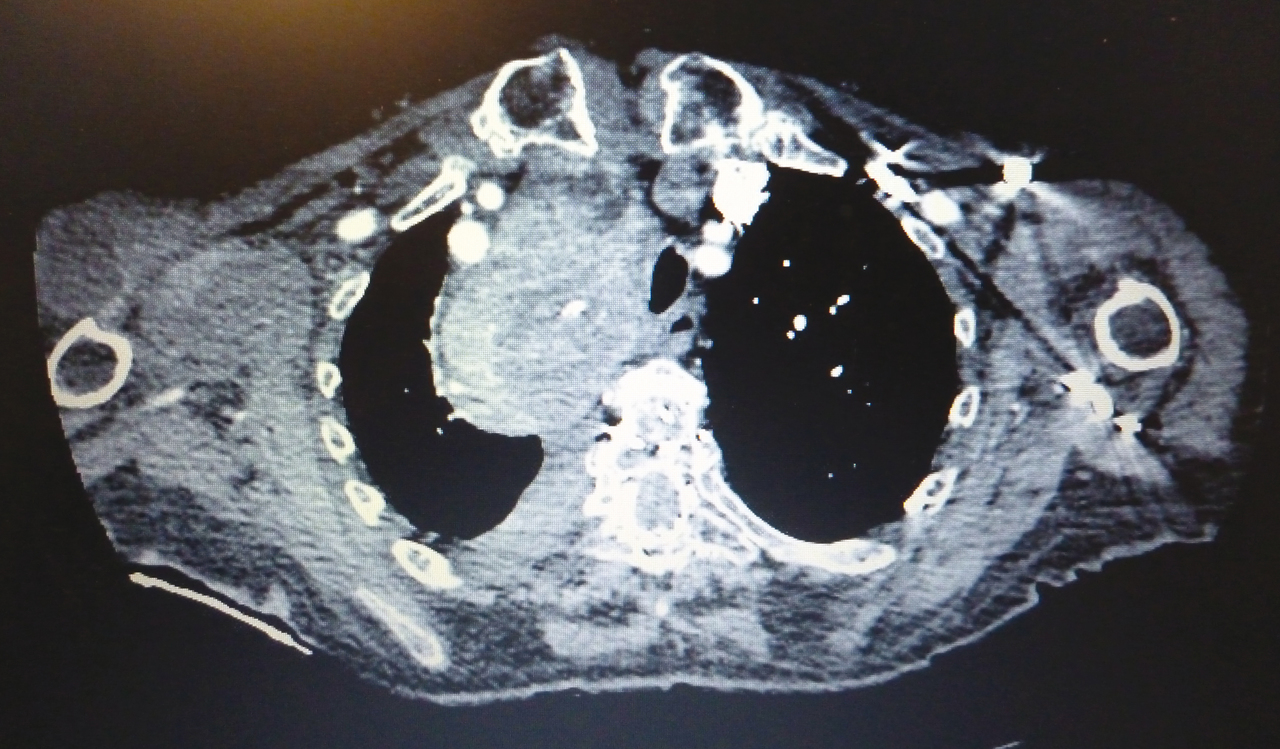

Il s'agit d'un goitre plongeant.

Cette photo provient de la collection du Pr Olivier Fain (Hôpital Saint-Antoine, Paris).